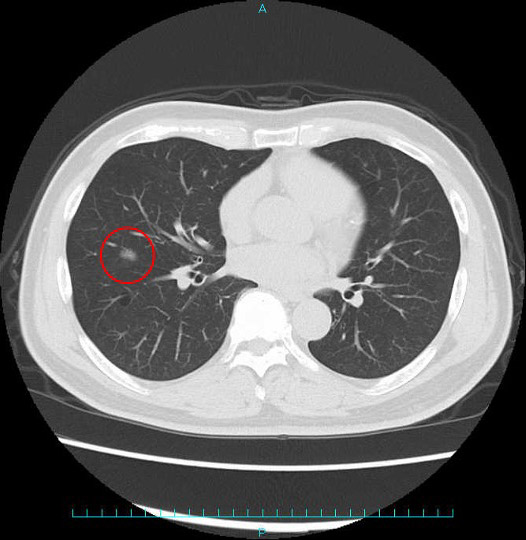

最初に必ず行うのが単純胸部X線検査ですが、2センチメートルより小さい腫瘍や、心臓や横隔膜、骨と腫瘍が重なる位置に存在すると発見が困難なため、次にCT検査を行います。CT検査とは、X線とコンピュータを組み合わせて行うもので、人体を輪切りの状態にして、その断面を画像にします。現在は1ミリスライスでの撮影が可能なため、直径5ミリメートル程度の肺がんやすりガラス陰影という、超早期の肺がんも発見することができます。また、後述する病期分類の決定にも有用です。

例:早期肺がんと進行肺がんのCT画像

早期肺がん